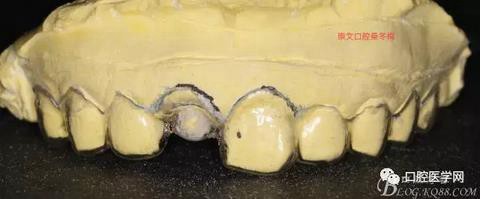

制作導(dǎo)板

戴入導(dǎo)板

纖維樁+樹脂核

樁道長14mm